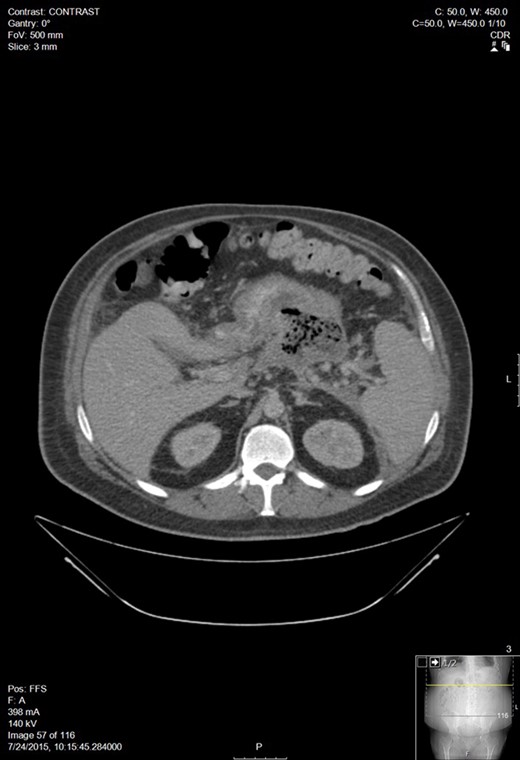

A 30-year-old man with a past medical history of hypertriglyceridemia presented to an outside ER with nausea, vomiting and abdominal pain. Lab studies were significant for pancreatitis (lipase 2730), hypertriglyceridemia (1594), blood glucose of 389 and BUN/Cr of 17/1.3. A CT of the abdomen showed AP. A subsequent lab draw showed BUN/Cr to 27/3.8, decrease in lipase to 565, increase in triglycerides to 4243, and a BNP 15. He was transferred to our facility following worsening hypoxemia. A CT scan was performed: representative sections shown below demonstrated walled off pancreatic necrosis (Fig. 1). He was in acute renal failure on presentation and started on continuous renal replacement therapy. The renal failure resolved, he completed a 7-day course of imipenem/cilistatin and was eventually discharged 11 days after admission.